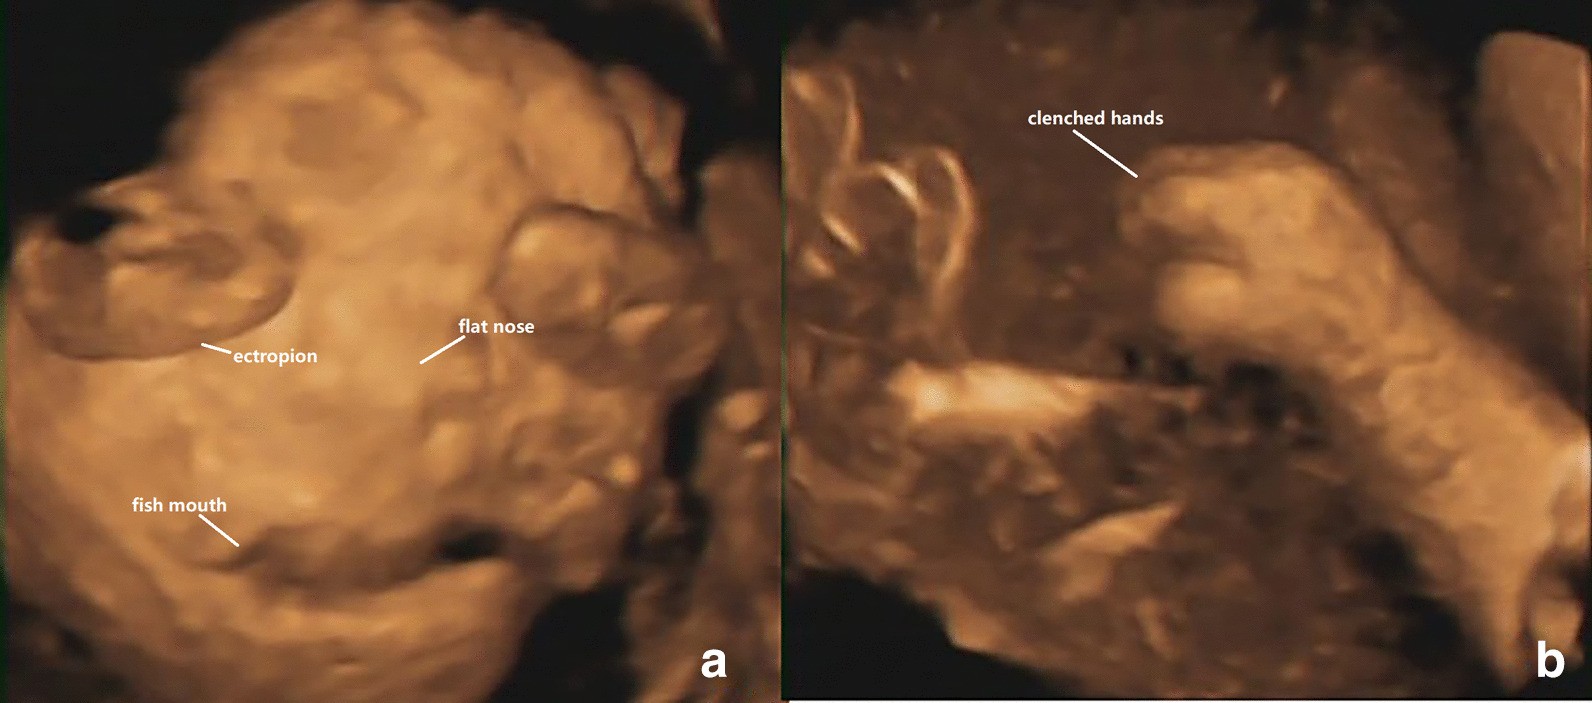

Fig. 3

From: Prenatal diagnosis of a rare variant of harlequin ichthyosis with literature review

a 3-D ultrasound: visual display of abnormal fetal face, include: ectropion, the nose flat. The mouth could not be closed and was like a fish's mouth. b 3-D ultrasound: excessive flexion of fingers